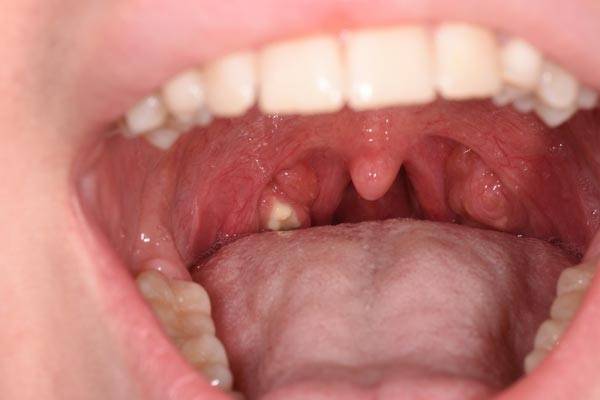

편도결석=편도결석은 우리 입안에 있는 편도선에 있는 구멍에 음식물 찌꺼기가 쌓여 생긴 것이다. 편도결석은 쌀알 크기의 작고 노란 알갱이로 다른 결석과 달리 딱딱하기보다는 말랑말랑하다. 편도결석이 생기면 심한 구취가 나고 침을 삼킬 때 목에 뭔가 걸린 듯한 느낌이 나기도 한다. 가래를 뱉거나 기침할 때 결석이 빠져나올 수도 있다. 보아스이비인후과의원 오재국 원장은 "생활 중에 저절로 제거되지 않는 경우 병원에서 흡입기로 제거해야 한다"며 "평소에 양치질 후 물로 헹굴 때 고개를 뒤로 젖히고 가글하는 게 도움이 된다"고 말했다. 수분을 조금씩 자주 섭취해 구강 인두를 건조하지 않게 하는 것도 중요하다. 편도결석은 재발이 잦은 편인데, 반복되면 편도결석이 주로 발생하는 편도를 절제하는 경우도 있다.